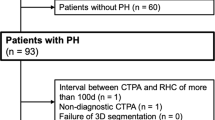

This retrospective study was approved by the institutional review board. Informed consent requirement was waived because of its retrospective nature. Records of all patients undergoing RHC, CTPA and transthoracic echocardiography for the initial diagnostic workup of suspected pulmonary hypertension in our institution between August 2013 and June 2015 were retrospectively reviewed (n = 94). Exclusion criteria were signs of chronic thromboembolic disease on CTPA (n = 13), an interval between CTPA and RHC of more than 30 days (n = 3), non-diagnostic CTPA (n = 3), missing RHC measurements (n = 1) or missing echocardiographic PASP measurements (n = 4) resulting in a final study population of n = 70 (Table 1). Signs of chronic thromboembolic disease on CTPA was chosen as an exclusion criterion because intraluminal thrombi can be expected to decrease the contrast-enhanced vessel lumen thereby resulting in falsely low vessel volume measurements. Patient characteristics (gender, height, weight, age) were extracted from the records; body surface area was calculated according to the formula by Du Bois and Du Bois [22].